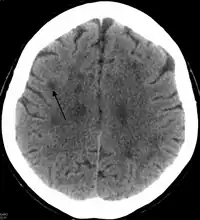

"CT showing a leukoencephalopathy "

An axial CT scan presenting a leukoencephalopathy, the base disorder to the family of disorders that HDLS falls under.

In HDLS, there is enlargement of the lateral ventricles and marked thinning or weakening of cerebral white matter.[6] The loss of white matter is caused by myelin loss. These changes are associated with diffuse gliosis, moderate loss of axons and many axonal spheroids.[1]